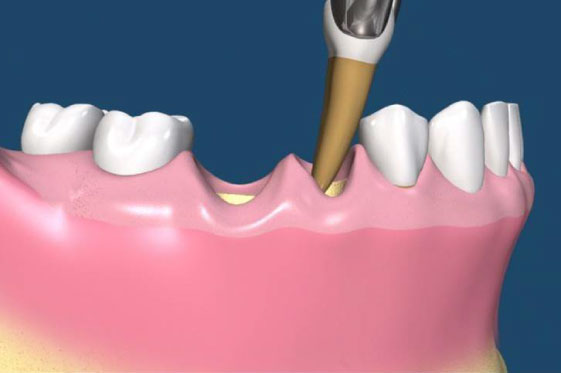

• 手術階段

第一期植體植入:精確測量可供植牙的牙孔,並植入鈦合金的人工牙根然後縫合,在手術後7天拆線。(2-3個月追蹤傷口複檢一次)一般植入的人工牙根需4-6個月才和骨頭結合。手術後72小時內,傷口若出現腫脹,在手術後24小時內可用冰敷來減輕腫脹情況,手術後的復原時期,需特別的清潔照顧。第二期植牙接出手術:經4-6個月骨整合後,進行第二次植體接出手術。